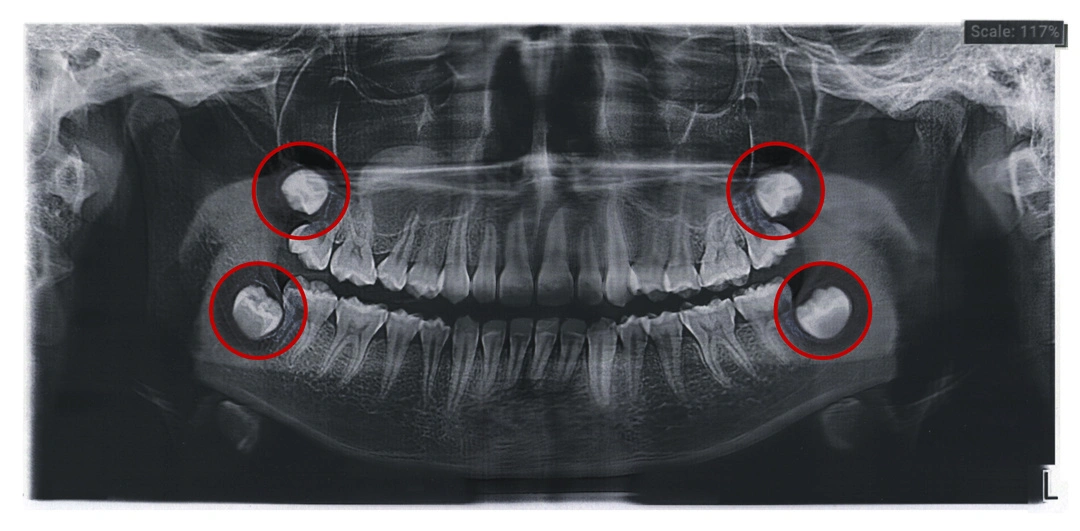

Dents de Sagesse : Symptômes, Extraction et Conseils

Les dents de sagesse, souvent problématiques, nécessitent parfois une extraction pour préserver la santé bucco-dentaire. Découvrez nos conseils et solutions.... Lire la suite.